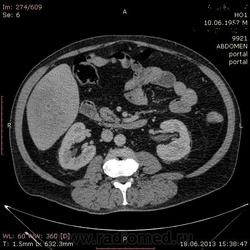

На абсцесс похоже

+1. Контраст вводили?

На мой взгляд, абсцесс.

Тоже за абсцесс.

Cпасибо , коллеги.Сегодня больного прооперировали диагноз абсцесс правой доли печени.Оказывается больной когда - то получил тупую травму живота, об этом нам не говорил.....